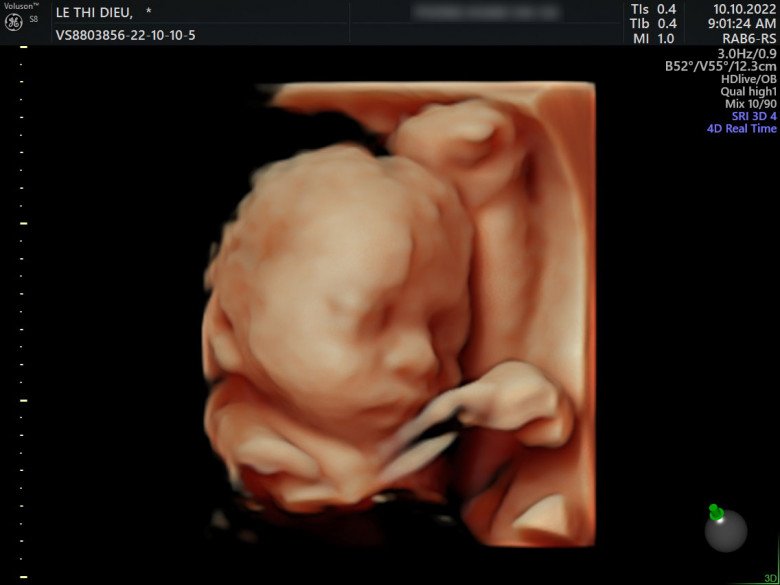

Mới đây, anh Phong hạnh phúc chia sẻ bà xã đã mang thai tự nhiên được 29 tuần. Ông bố trẻ tâm sự, vợ chồng anh quyết định “thả” ngay sau khi cưới và một tháng sau đó thì bất ngờ nhận tin vui. Cảm giác khi ấy của hai vợ chồng vô hạnh phúc, không biết diễn tả như thế nào.

Hiện tại, Huyền Diệu đã mang thai được 29 tuần.

Trộm vía đến giờ thì sức khoẻ của hai mẹ con đã tốt rồi. Vợ mình đã tăng được 8kg. Hai đứa đi siêu âm nhìn em bé rất thích”, anh Phong nói thêm.